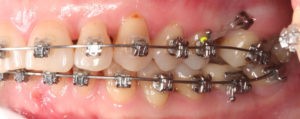

Искривление окклюзионной кривой (плоскости смыкания зубов), возникшее в результате парадонтита, успешно удалось устранить, используя накусочные брекеты на верхних резцах и микроимплант, установленный во фронтальном участке нижней челюсти: